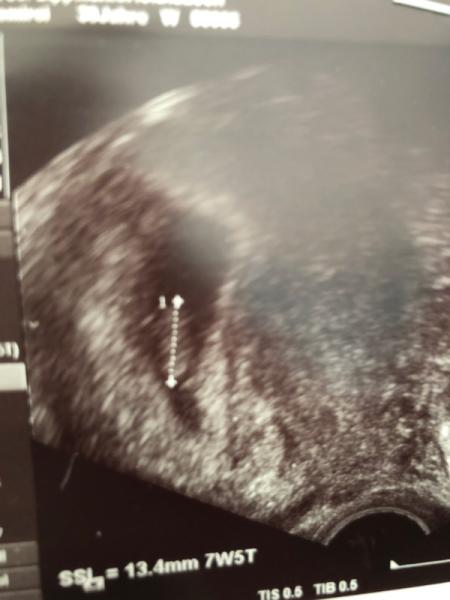

Hallo liebe mamis, ich bin heute bei 7+5 und hatte meinen 2.frauenarzt termin. Wir haben das winzige herzchen schlagen gesehen Ich bin echt froh und sehr dankbar. Eins muss ich aber sagen beim ultraschall bild ist das embryo so komisch unscharf zu erkennen. Ist das normal? Ich denke wegen dem ultraschall gerät oder? Was sagt ihr dazu? Laut frauenarzt alles in ordnung. Bild füge ich mit bei.

Bild zu 2. termin hinter mir... - Forum für Januar - Mamis

Glückwunsch!!! Die Unschärfe ist normal, war bei mir 6+6 auch so. Und die Größe ist ja auch optimal